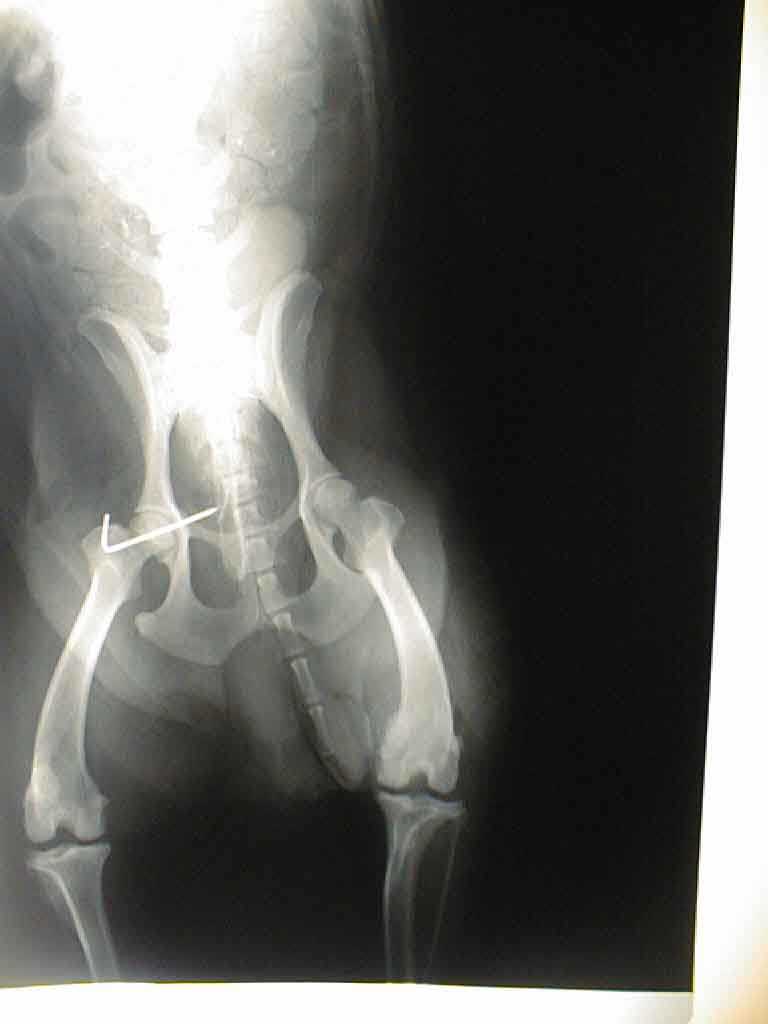

Lendenwirbelfraktur L6

Fixation der Wirbelsäule mittels Querverbolzung durch beide Darmbeinflügel und Kreuzbein,

Drahtcerclage zwischen L6 und L7